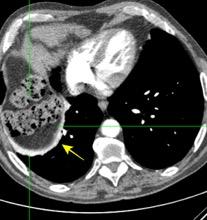

T. mixto de células germinales del testículo izquierdo

Nódulos pulmonares múltiples. (flechas verdes). Masas paratraqueales. (flechas amarillas). Dudoso ensanchamiento retrocrural (flechas negras). sigue….

Ttawfik A et al. Trans-diaphragmatic Pathologies: Anatomical Background and Spread of Disease on cross-sectional Imaging. Current Problems in Diagnostic Radiology. 2021.

T. mixto de células germinales del testículo

izquierdo Metástasis pulmonares. (flechas verdes). Ganglios paratraqueales. (flechas amarillas). Ganglios retroperitoneales (flechas negras)

Tawfik A et al. Trans-diaphragmatic Pathologies: Anatomical Background and Spread of Disease on cross-sectional Imaging. Current Problems in Diagnostic Radiology. 2021.